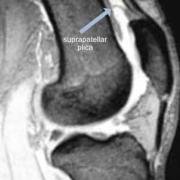

This MRI shows a similar view where the arrow is pointing to a complete suprapatellar septum dividing the cavity into two - the closed bursa (above) and a small pouch below. This may confuse the novice surgeon during arthroscopy.